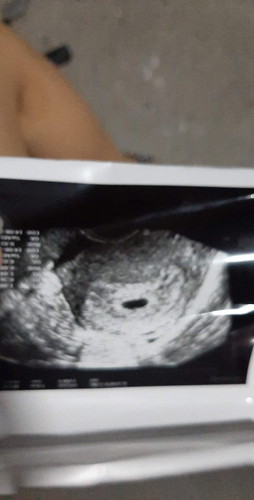

ไปซาวมา หมอบอกยังเป็นไข่อยู่ ถุงน้ำ 8 มิลแล้ว เดือนหน่อยๆแล้ว